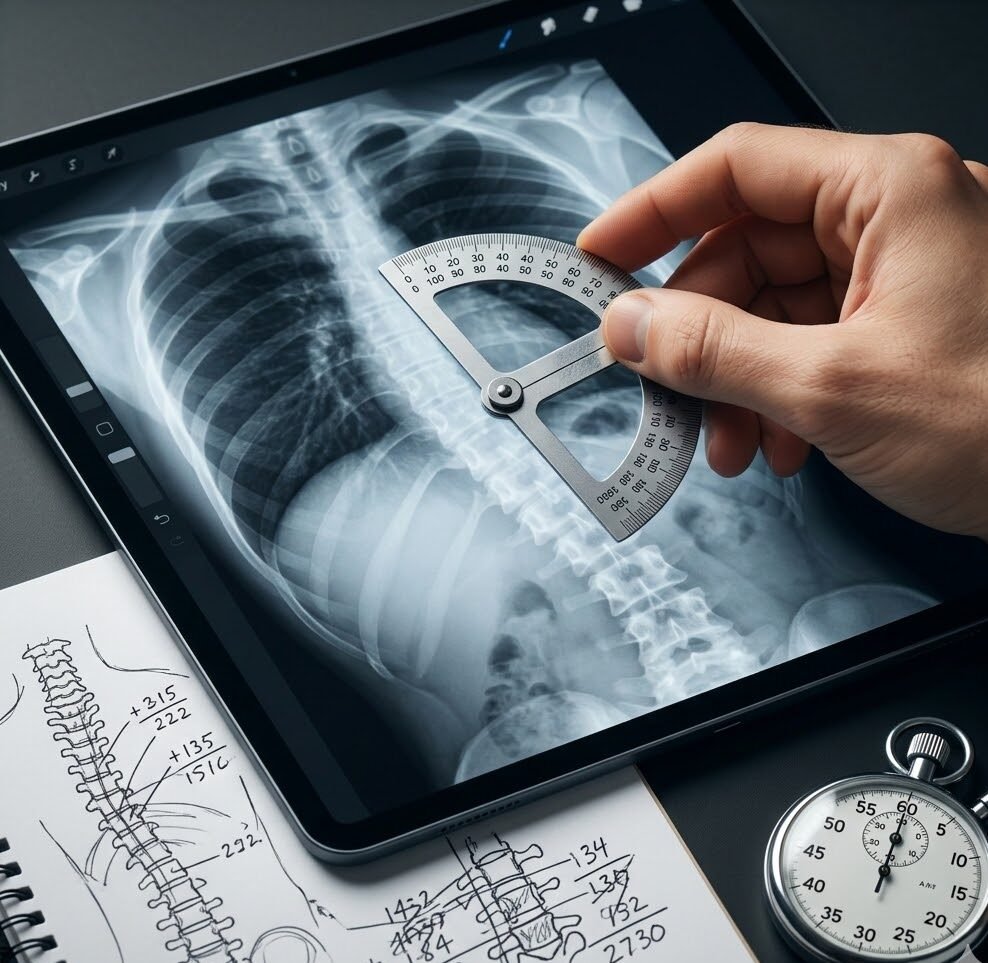

Fast & Efficient Measurements

Generates measurements in ~3 seconds, significantly reducing the time required for manual analysis.